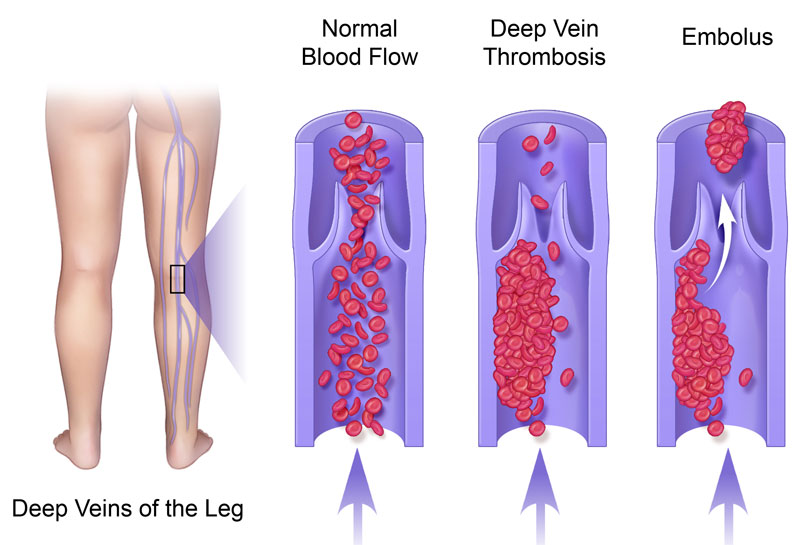

vein thrombosis deep dvt danger clot blood prevention

dvt thrombosis vein

thrombosis vein dvt veins embolism pulmonary drugwatch lungs vessel

thrombosis vein dvt blood